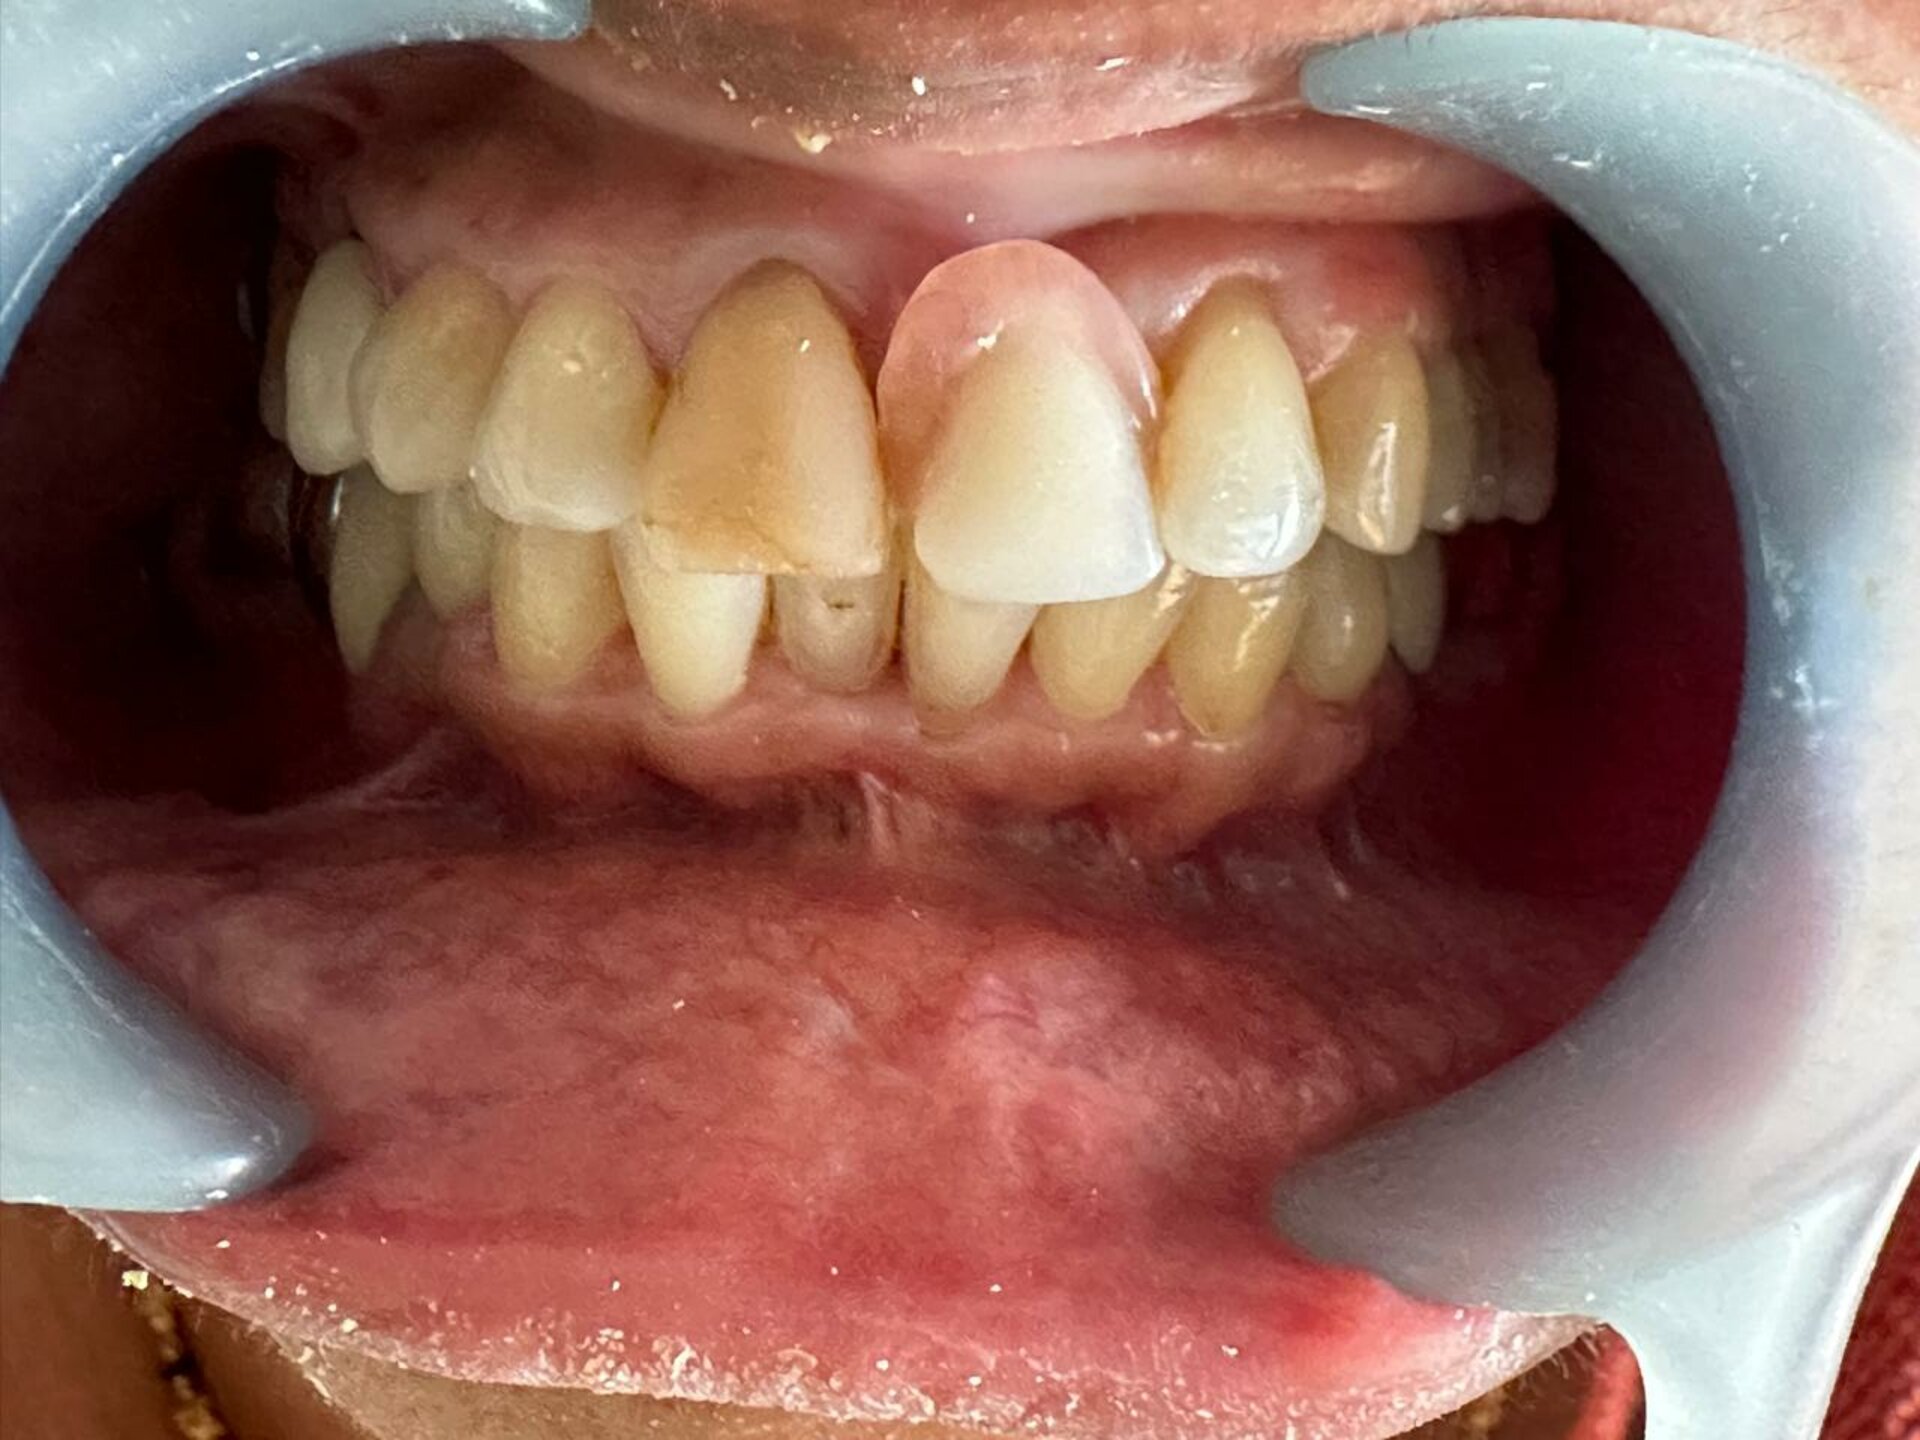

Dr. Gautami Phadke, Consultant Dental Surgeon and Root Canal Specialist in Karve Nagar, Pune, recently transformed the smile of a 60-year-old patient ...